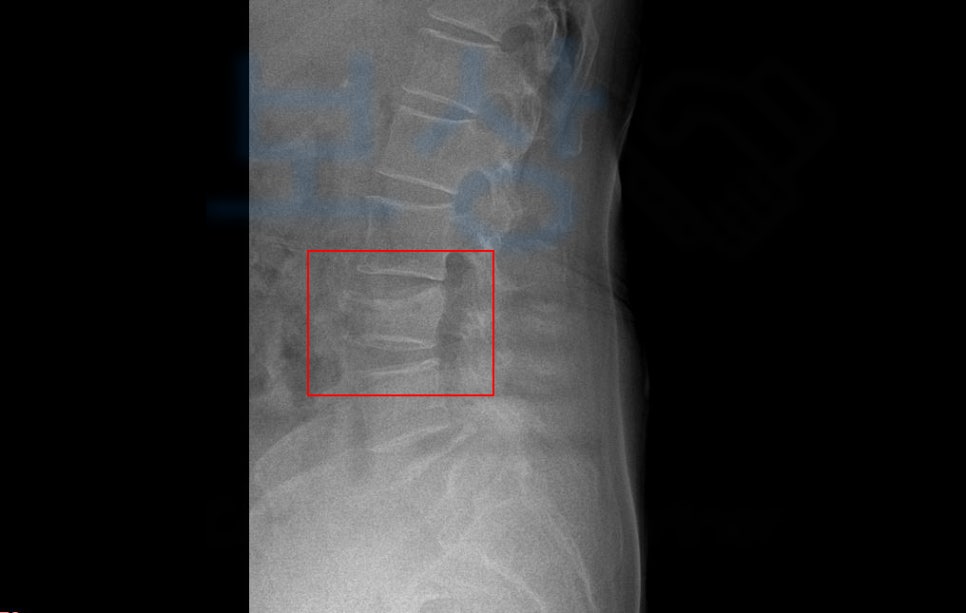

위 사진이 사고 이후 2개월이 경과한 엑스선 사진입니다.

mri사진도 보시면 심각하게 척추체가 찌그러진 것을 보실 수 있죠. 이 사고로 주치의는 수술을 권유했으나, 척추에 수술을 하는 것에 대해 여러 이유로 수술보다는 보존치료를 선택하셨는데요,